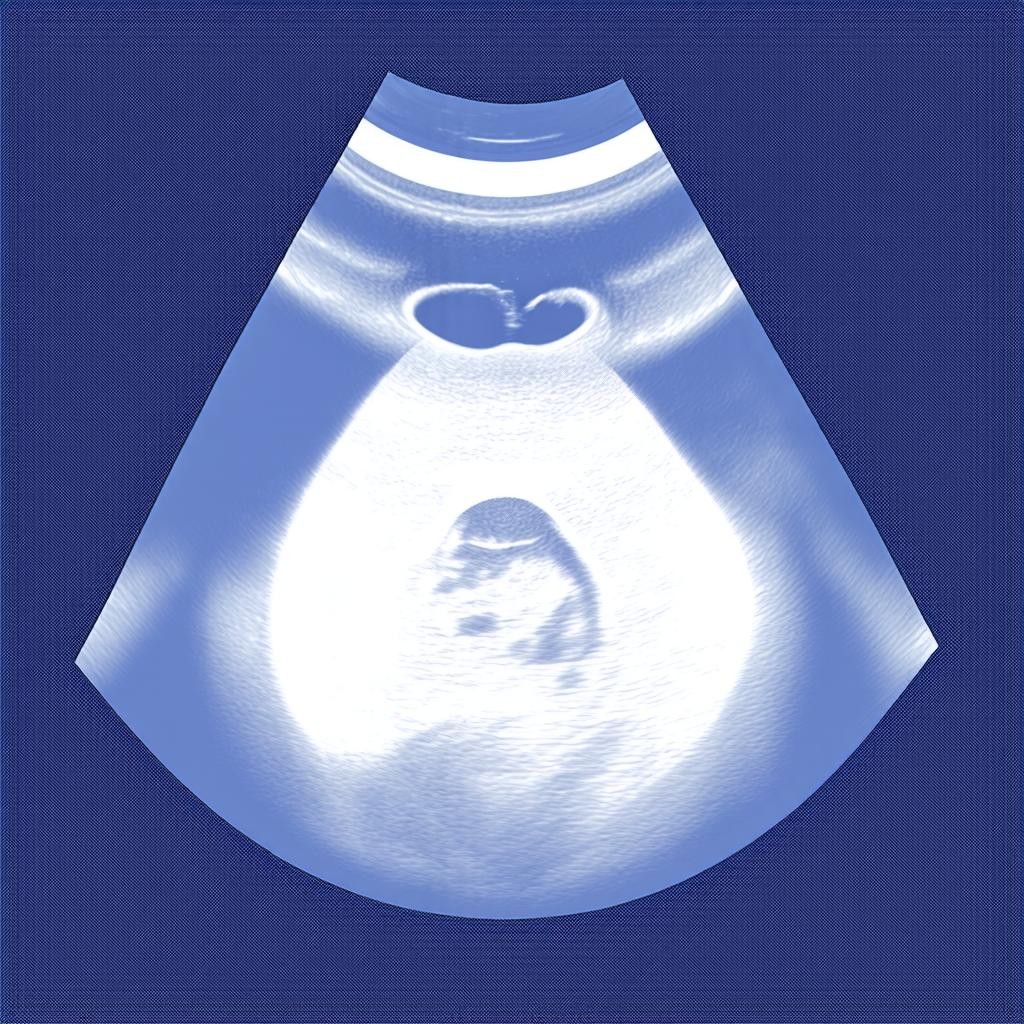

Что покажет УЗИ на 4 неделе беременности?

На 4 эмбриональной неделе УЗИ может обнаружить следующие изменения:

- Плодное яйцо: УЗИ может показать наличие плодного яйца в полости матки, что подтверждает беременность.

- Желточный мешок: Это временный орган, который питает эмбрион до формирования плаценты.

- Толщина эндометрия: Утолщенный эндометрий свидетельствует о подготовке организма к беременности.